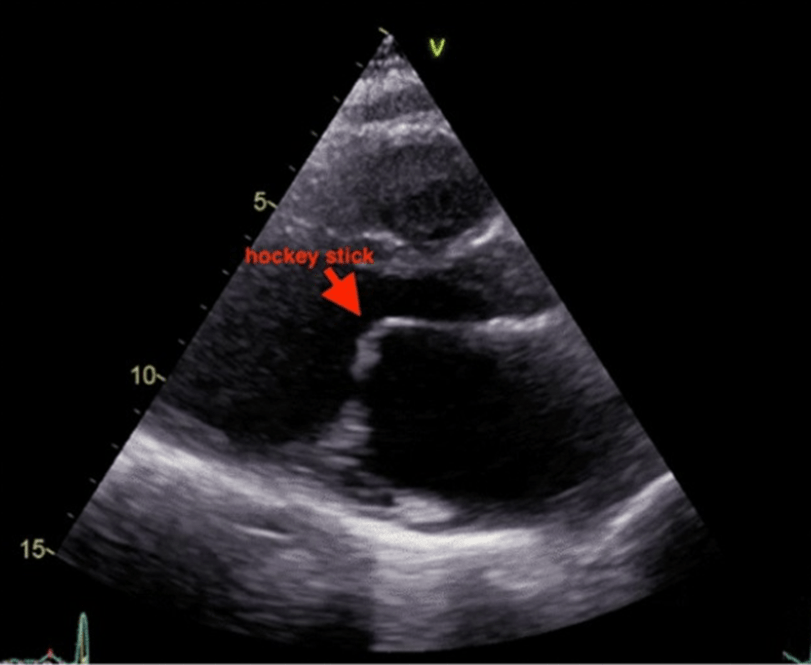

46y/o/F with new Afib has an apical murmur and undergoes a TTE. What is the valvular dysfunction and likely etiology?

Rheumatic Mitral Stenosis.